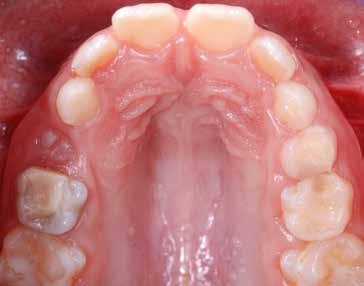

Presentazione del caso > F.V, bambino di cinque anni, presenta una malocclusione di II Classe scheletrica, III Classe dentale molare e canina destra e sinistra, morso inverso anteriore. Le arcate dentali mostrano usura degli elementi dentari anteriori a causa dell’occlusione patologica. Le linee mediane, superiore ed inferiore, sono centrate; il frenulo labiale superiore patologico per un’eccessiva estensione inter-incisale.

Dall’esame clinico si evince la III Classe dentale, l’inversione anteriore e l’over-jet negativo.

Considerazioni > L’analisi cefalometrica ad inizio trattamento dimostra la II Classe scheletrica con protrusione del mascellare superiore e prognazia mandibolare; tendenza alla crescita verticale. L’esame clinico evidenzia una protrusione mandibolare funzionale.